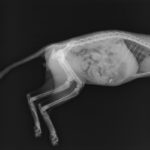

Podczas pierwszego RTG oprócz chorego ogonka odkryliśmy również mały niezidentyfikowany obiekt w brzuszku Pucka. Podejrzewaliśmy odłamek śrutu. Kotek czuł się dobrze, więc nie było wskazań do operacji. Dopiero teraz Pucuś zaczął intensywne wylizywać miejsce obok kikutka. Okazało się, że to ten sam obiekt – kawałek kości próbujący wydostać się na zewnątrz. Biedaczek błyskawicznie znalazł się na stole zabiegowym i na dobre pozbył się intruza.Teraz Pucek jest w pełni zdrowy i czeka na swojego nowego opiekuna.